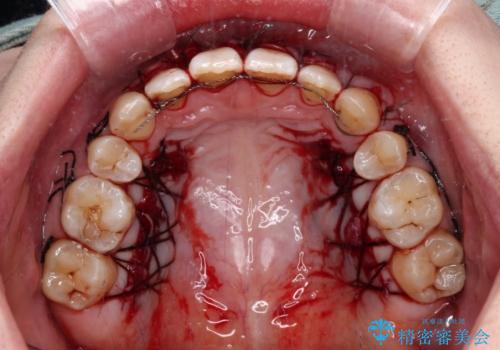

歯肉退縮に対して、上顎からの結合組織移植術(CTG)により、歯根の被覆を行うとともに、歯肉の厚みを増すことで将来の退縮リスクを抑制することとしました。

抜歯矯正を行ったため、採取可能な歯肉の量が少なくなるため、被覆量が不十分の場合には、追加で手術を行うことで患者様の了解を得ました。

必要な被覆量が多かったため、満足のいく被覆を達成するには2度の手術が必要と思われましたが、生着がよく、術後の注意事項を徹底したことで、十分な被覆量を達成することができました。